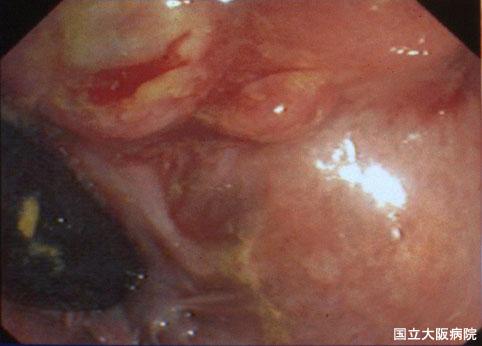

症例提示(所在地,施設名等): 大阪府・ 大阪医療センター

疾患(病理主体)の分類悪性黒色腫/

部位(臓器別)大腸/直腸

検査方法内視鏡

病変の最大径(ミリ)40以上

腫瘍の深達度mp